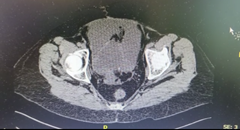

A computed tomography scan of the abdomen and pelvis was performed, showing free abdominal fluid and a lesion in the bladder dome, diagnosing uroperitoneum.

Figure 2 Computed tomography of the abdomen and pelvis. Bladder perforation is evident, with free peribladder fluid.